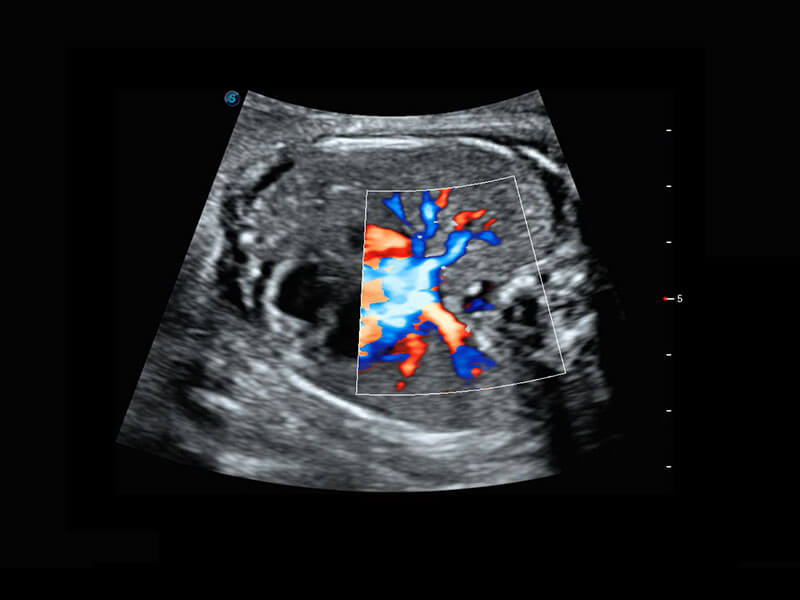

胎心筛查

P60搭载一系列胎儿心脏成像技术,实现精细的胎儿心脏评估。

• 右室双出口